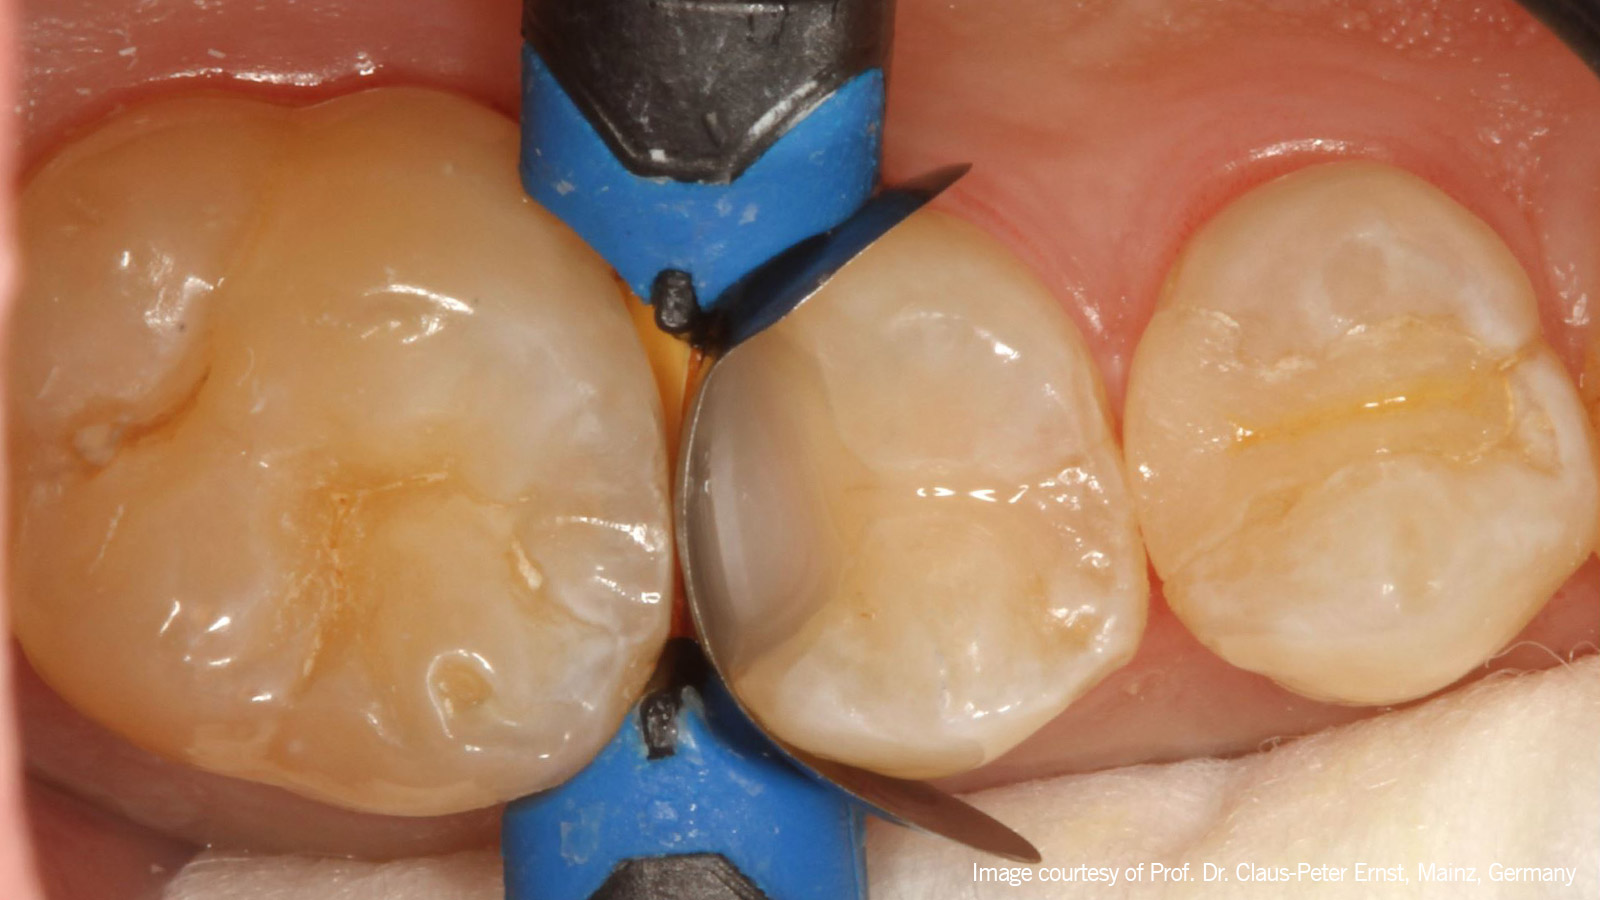

The first layer

De eerste laag in de proximale box en in de uitgebreide occlusale fissuur werd gecreëerd met Venus Bulk Flow ONE in een "klassieke" flow laagdikte van 1-2 mm.

self-adapting colour ONE

Vervolgens werd Venus Pearl in de zelfaanpassende kleur ONE als toplaag gebruikt.